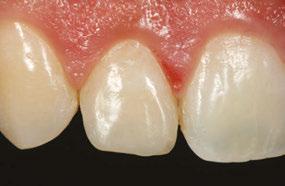

Case 3

A 4-year-old female presented with existing Silver Modified Atraumatic Restorative Technique (SMART) style restorations on #D, #E, #F, #G, and caries on other teeth. These anterior lesions

had been previously treated using SDF and covered with a HVGIC in a strip crown form. Though her lesions were stable from the clinical success of the SDF and HVGIC, these restorations were starting to fracture and demonstrate loss of material. The family wanted a more esthetic treatment option that would have a longer survivability. Additionally due to her high caries risk nature, a full coverage restoration with NuSmile® ZR anterior crowns were a more ideal solution in stabilizing her extensive decay pattern and covering staining from SDF therapy (Figure 4).

Figure 3: NuSmile® ZR Crowns were selected as a cementable full coverage restoration. At 6-month recall, apical tissues were healed with excellent gingival health Figure 4: SMART style restorations that were definitively restored with NuSmile® ZR Crowns as an esthetic option to cover SDF staining